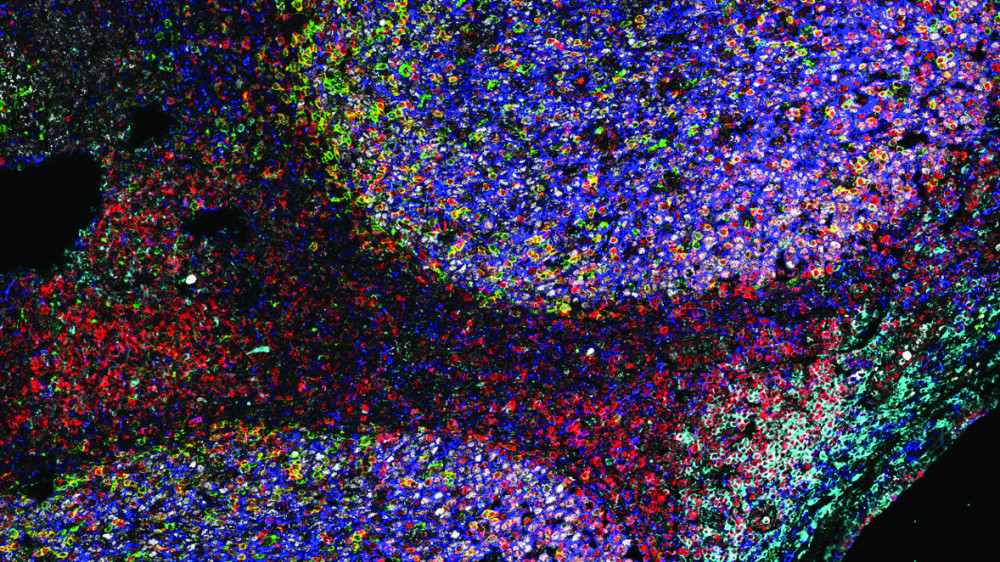

Tonsil

An animal-free organoid model of the adaptive immune response to support the rapid development of broadly protective vaccines.